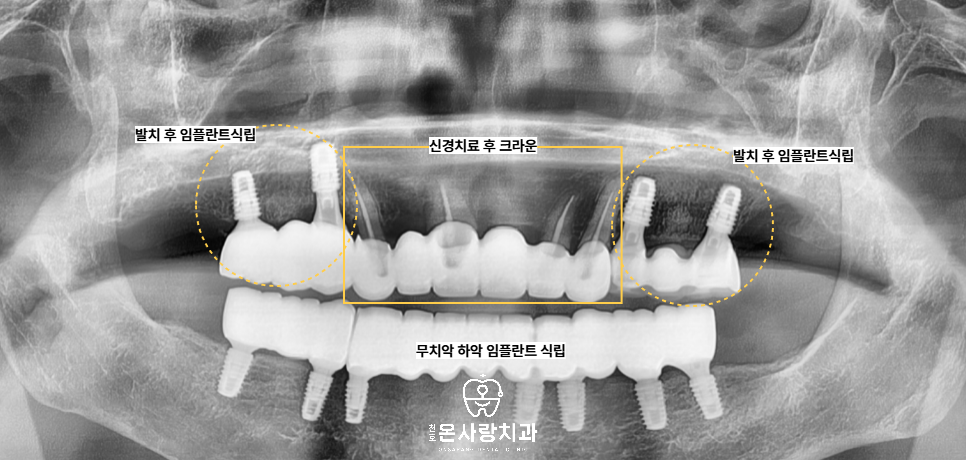

특히 전체 치아가 없는 경우라도

여러 개의 임플란트를 식립하여

전체 치아를 보철물로

제작하여 장착하면 자연치와

유사한 기능과 심미성을

회복할 수 있습니다.

이번 환자분의 경우 아래쪽은

완전 무치악 상태로

아래쪽에는 전체 임플란트

식립을 계획하였습니다.

위쪽은 오른쪽 위의

어금니부위를 제외한

대부분의 치아가 남아 있었지만,

전반적인 치조골 흡수와 염증이 심해서

치주상태가 불량한 보철이 되어있는

치아는 모두 발치가 필요했습니다.

다만 전치부는 잇몸 상태와

치근 길이가 양호하여

신경치료 후 크라운을 씌워

가능한 살리기로 하였습니다.